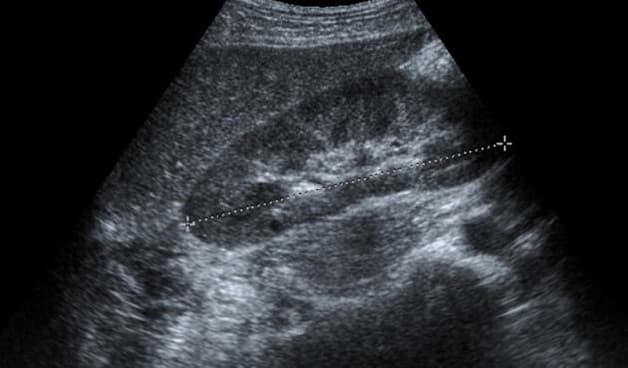

Siêu âm là phương pháp đơn giản, nhanh, không xâm lấn nên không ảnh hưởng đến sức khỏe của người bệnh. Qua hình ảnh siêu âm bác sĩ sẽ quan sát được hình dáng và trạng thái của gan có điểm bất thường nào không. Gan có vấn đề sẽ gồ ghề ở bề mặt, xuất hiện các khối u,… Đối với siêu âm màu còn có thể quan sát rõ ràng các mạch máu và hướng chảy của chúng để phát hiện vấn đề.

Phương pháp siêu âm đàn hồi mô gan được đánh giá tốt nhất hiện nay nhằm phát hiện tổn thương trong nhu mô gan và mức độ xơ gan. Khi khám bệnh nhân sẽ nằm ngửa, tay phải đặt sau đầu. Bác sĩ khám sẽ đặt đầu dò lên da kẽ liên sườn vị trí thường sinh thiết gan rồi ấn nhẹ và đo kiểm tra 10 lần liên tục cùng một vị trí. Máy sẽ tính toán ra chỉ số trung bình qua các lần đo và đưa ra con số cụ thể.

Phương pháp này dễ thực hiện ngay cả với các bệnh nhân béo phì, béo bụng. Bên cạnh đó các cơ quan khác trong cơ thể cũng có thể áp dụng phương pháp này.